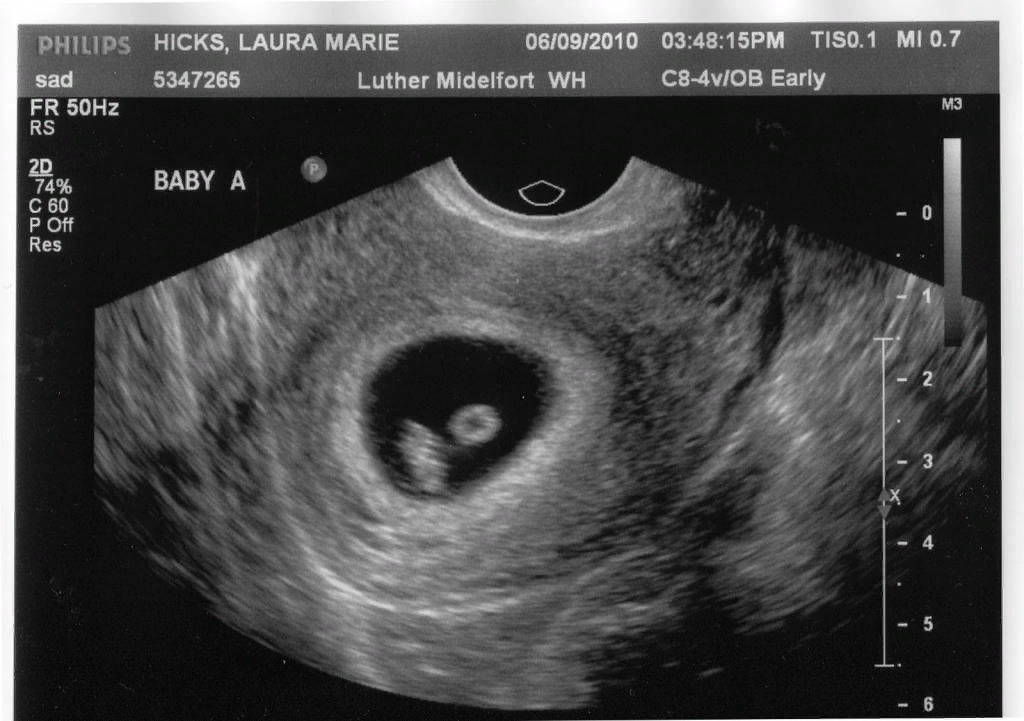

Во многих странах Европы до 12 недели беременности не дают препаратов прогестерона и вообще не рекомендуют сохранять малыша, если есть угроза выкидыша.

В Германии, например, есть важный критерий – сердцебиение плода. Т.е. если есть плодное яйцо, а сердцебиения нет, не рекомендовано лечение вовсе, кроме витаминов и отдыха. Если через неделю или две появляется сердцебиение, то ребёнок развивается в норме, и гормоны и некоторое лечение уже могут назначить. Если нет признаков жизни, то направляют на чистку с возможностью получить генетический анализ за счёт государства.